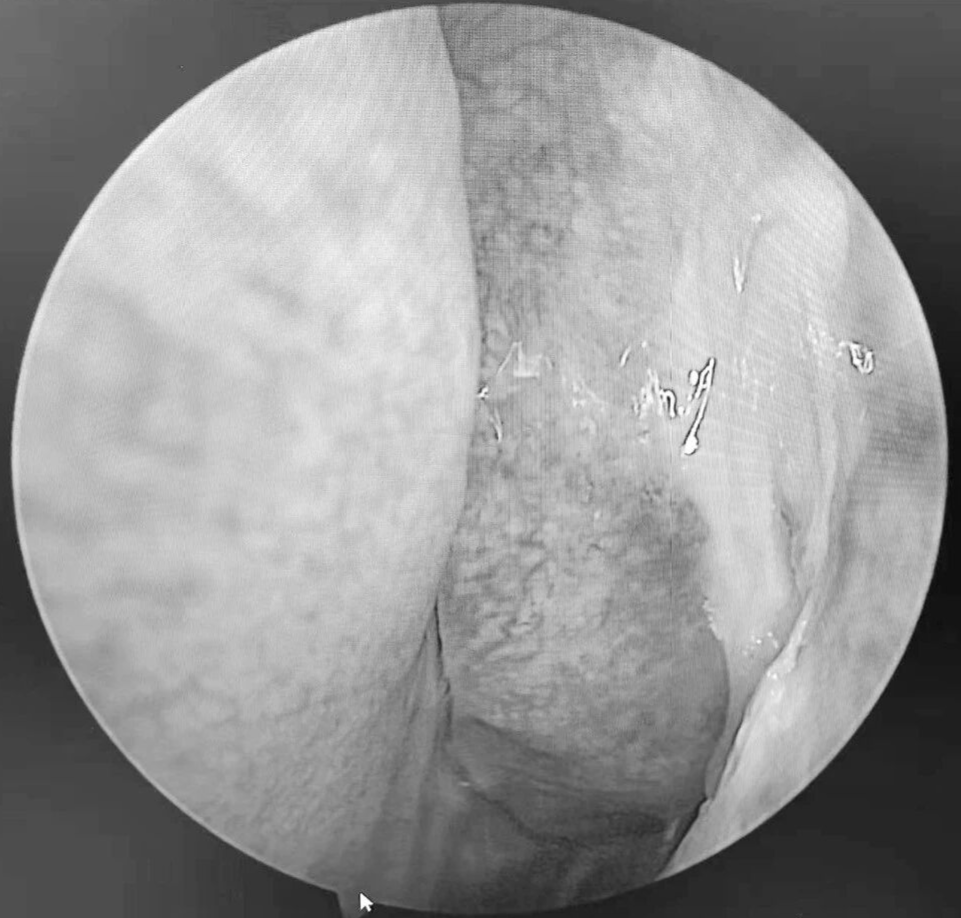

患者梁某(化名)因反复鼻塞、流脓涕伴头痛2月余入院,经检查确诊为急性鼻窦炎、双侧乳突炎,药物治疗后症状未缓解且并发筛窦脓肿到我院耳鼻咽喉科二区住院,科室团队快速完成术前评估,为患者制定个性化手术方案,在全麻下精准实施经鼻内镜手术,开放病变窦腔、清理脓液,术中损伤小,仅用吸收性明胶海绵止血。术后通过专业的鼻腔冲洗指导、药物治疗管理及定期内镜复查,有效促进术腔黏膜修复,降低复发风险,助力患者实现快速康复。

我院耳鼻咽喉科二区以微创内镜手术为特色,面对急性鼻窦脓肿这类需及时干预的病症,能通过高效术前评估、优化手术流程,精准去除病灶,避免并发症发生。手术前后规范用药配合专业术后护理,包括鼻腔冲洗指导与定期内镜复查,有效降低复发风险,践行快速康复外科理念。